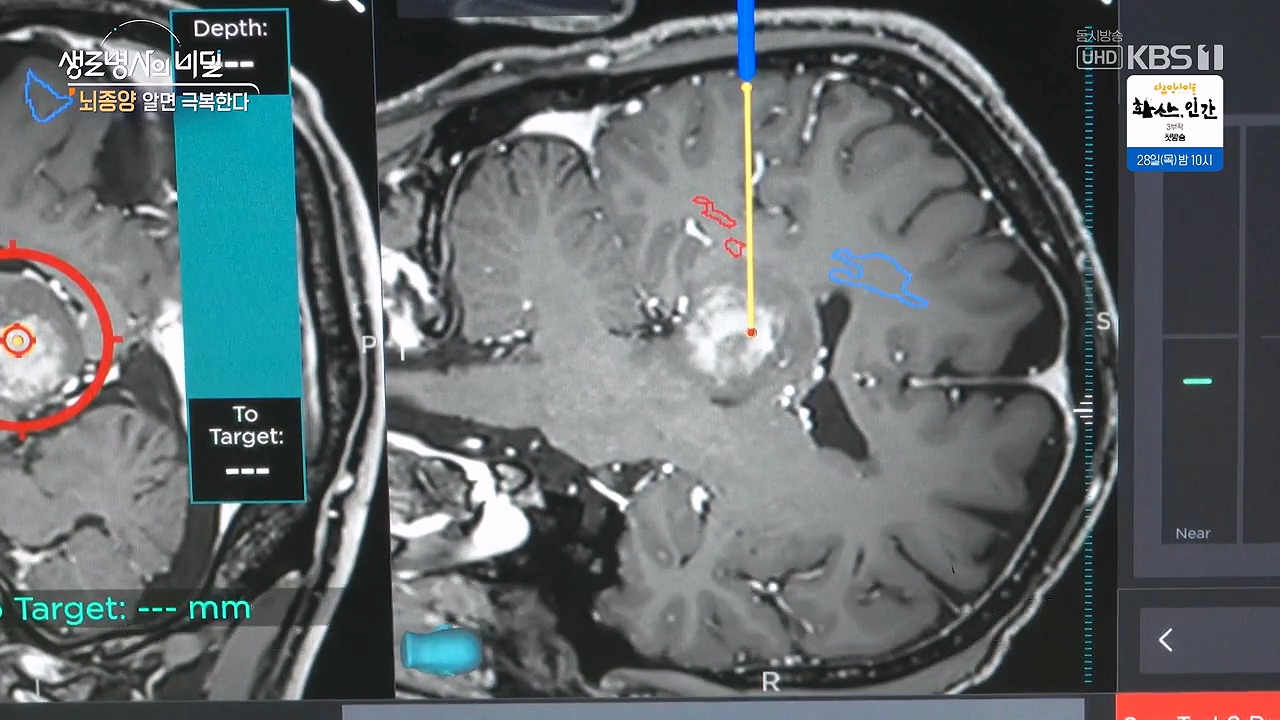

- 정위적 생검술 : 내비게이션 활용 원발성 중추신경계 림프종 사례

이재철 씨는 ‘5-ALA’를 활용한 개두술을 진행했다. 수술 전 5-ALA라는 특수 형광물질을 투여해 종양을 염색하고 염색된 종양만을 정교하게 제거할 수 있는 수술법으로 이재철 씨의 뇌종양은 성공적으로 제거되었다.